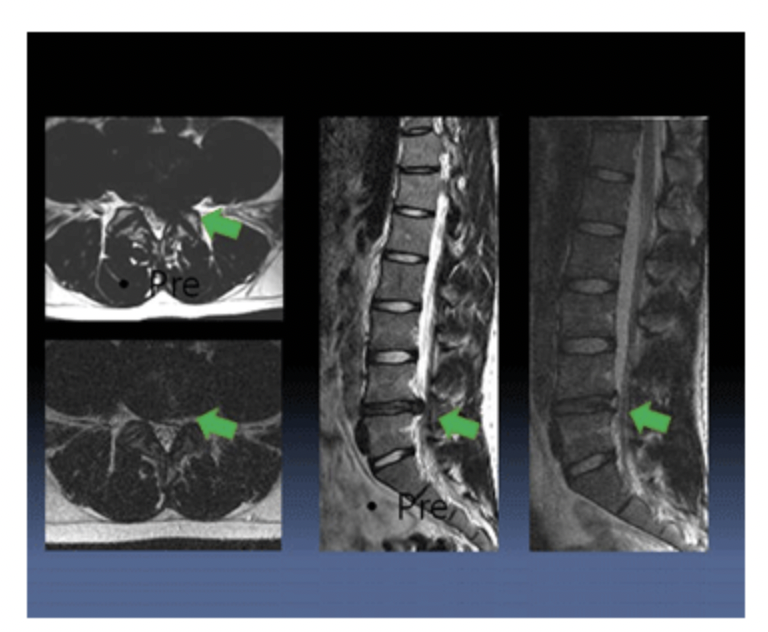

진단

요추부 추간판 탈출증의 진단을 위해서는 하지 직거상 검사를 시행한다. 하지 직거상 검사는 침대에 누운 상태에서 한쪽 다리를 무릎을 편 상태로 들어 올려 통증 발생 유무를 확인해 보는 검사로 요추 추간판 탈출증 환자의 경우 들어 올린 다리 뒤쪽으로 뻗치는 통증이 발생하여 다리를 들어 올리는데 제한되는 양상을 보인다. 그 외 다리의 근력, 감각 등을 확인하며 심부건 반사 이상 (슬개건 반사, 아킬레스건 반사 소실) 등을 확인한다. 그 외 x-ray, MRI, CT 검사를 통해 디스크 탈출 정도를 사정한다.